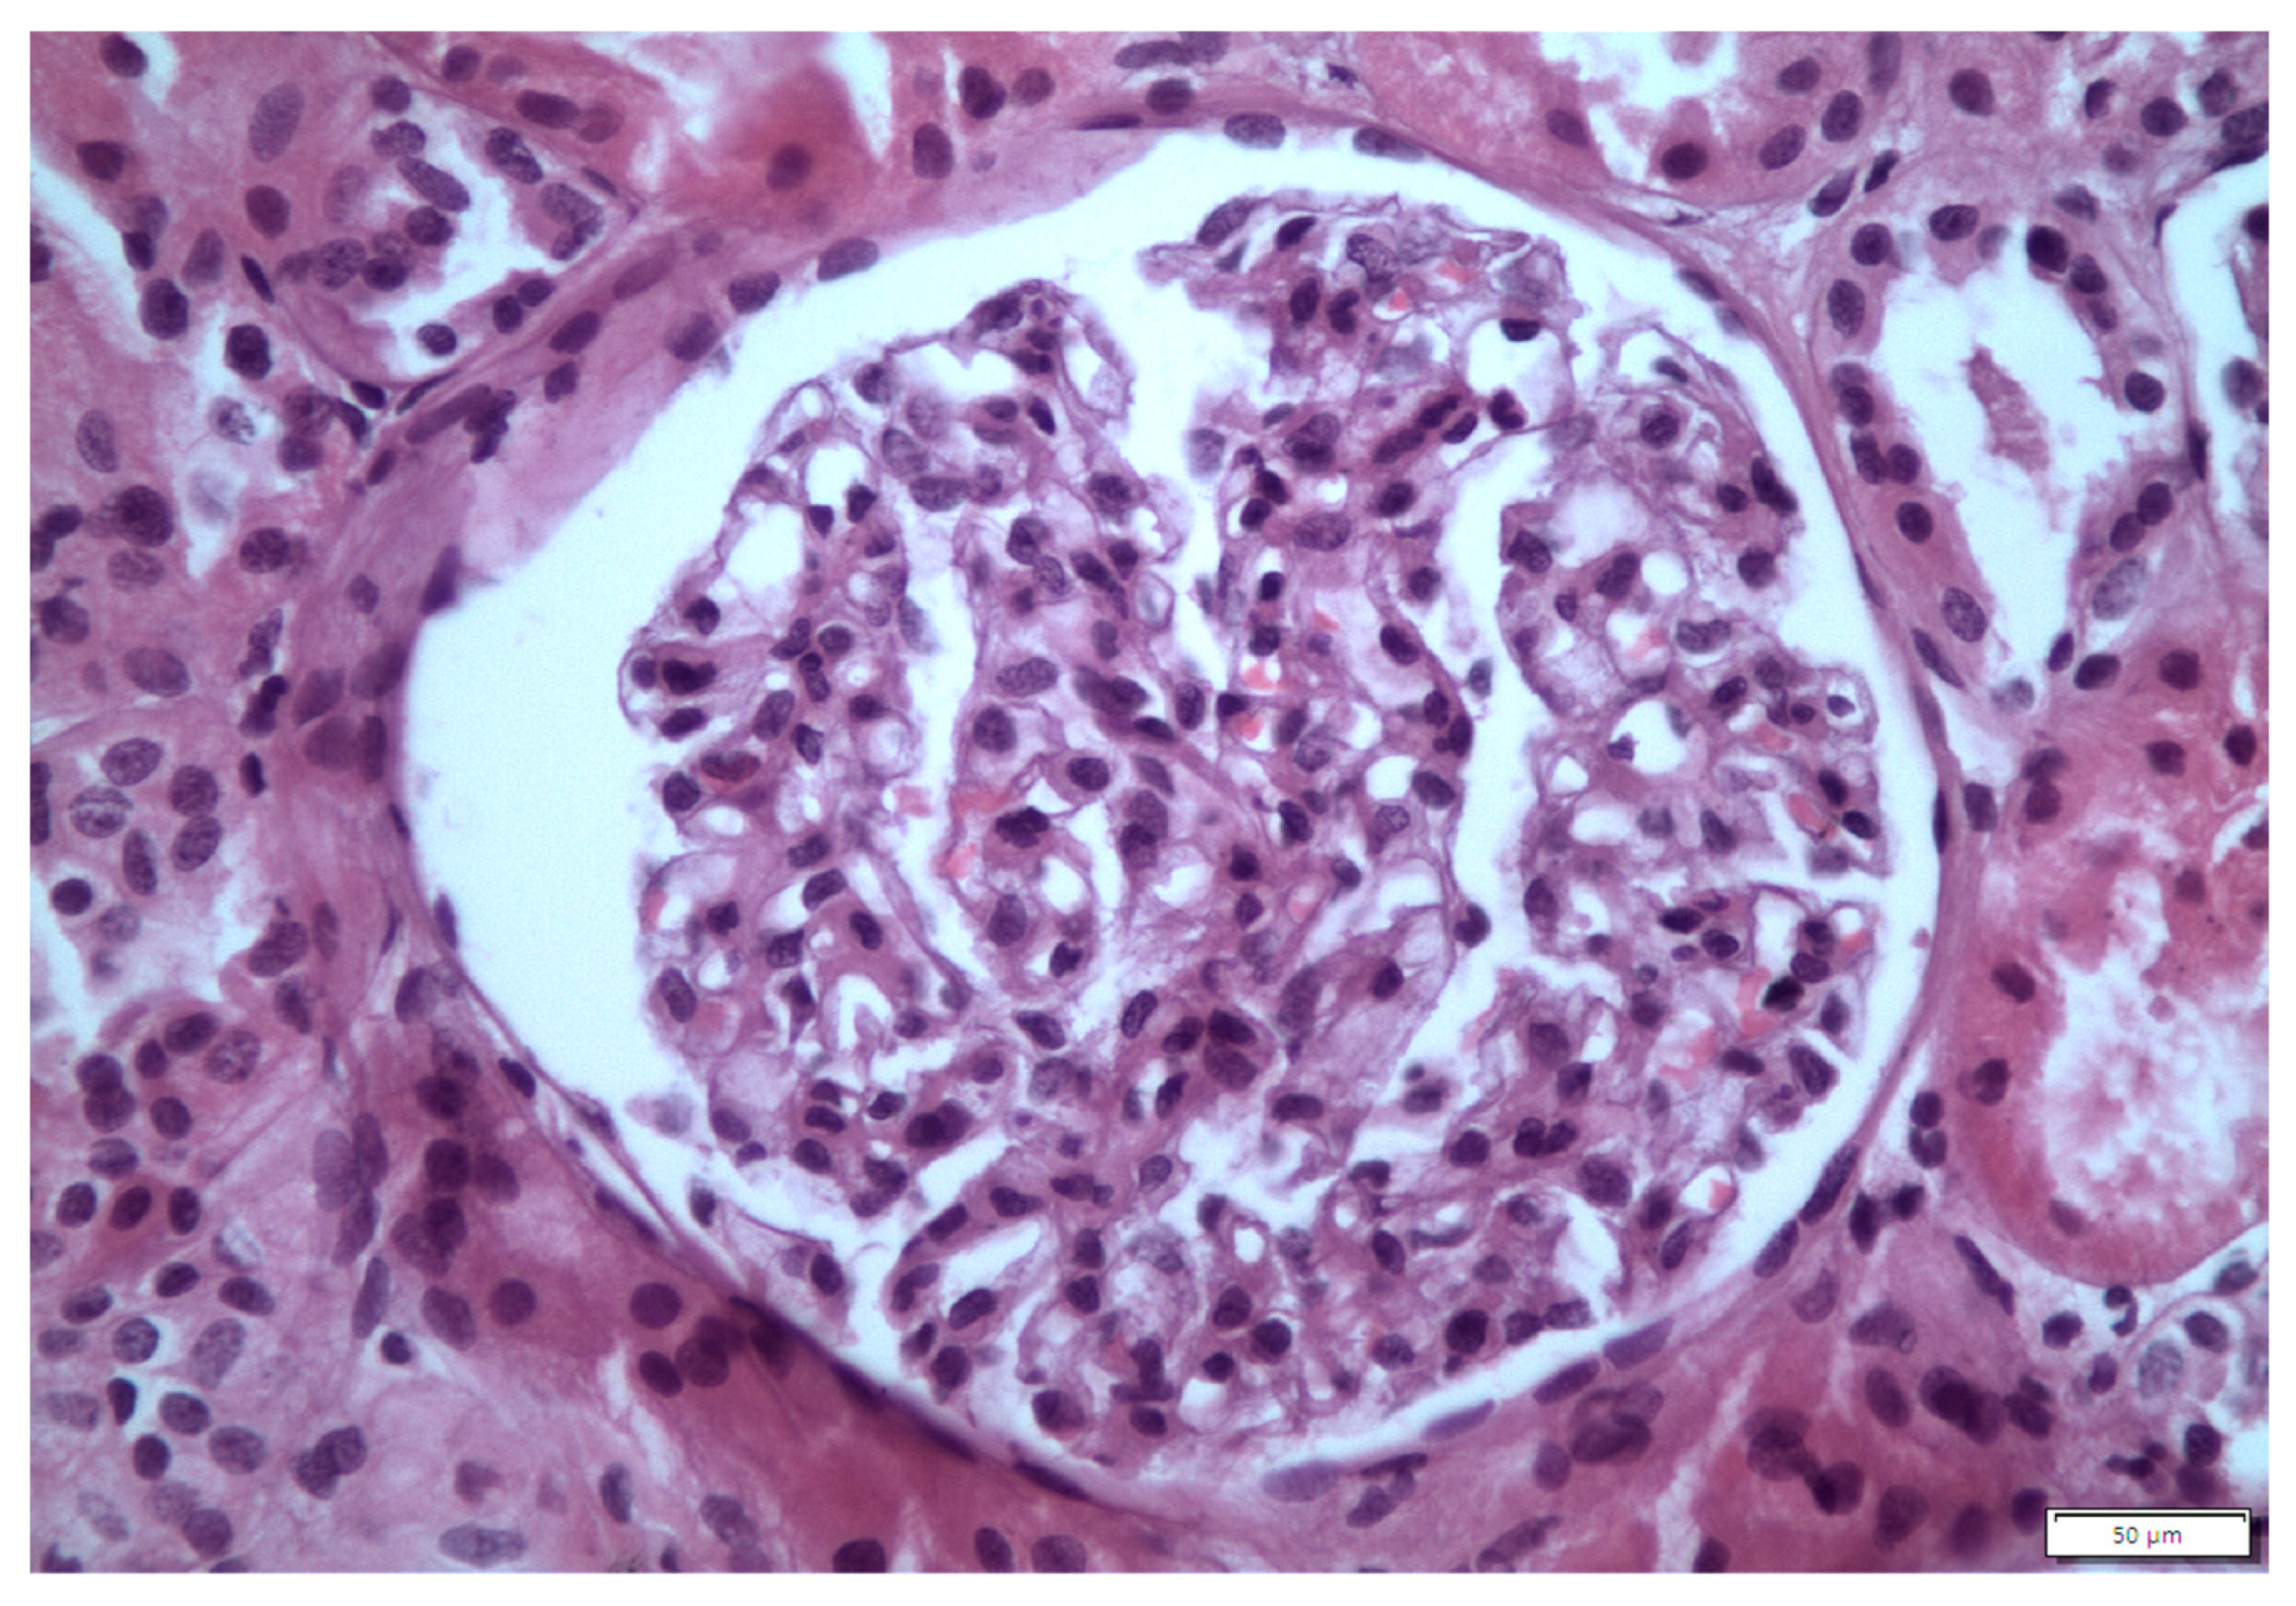

2. Case 1 Description: MCD Associated with Tamoxifen